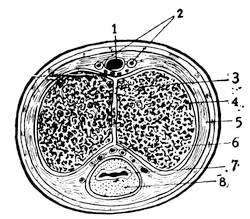

D. The External Genitals

At the time when the urethra, the sexual ducts and the intestine still open into the sac-like tube, the so-called cloaca, there is distinguishable on the exterior surface of the body, corresponding to the position of the cloaca, a certain depression called the cloacal depression. When the intestine is separated from the cloaca by the septum, the later perineum, the exterior cloacal depression is cut into two, the anal and the urogenital depressions. Between the urogenital depression, later called the genital groove, exteriorly and the urogenital sinus interiorly, there is only a dividing membrane, the urogenital membrane which later on breaks through and transforms the entire sinus into a shallow depression, termed the vestibule.

Before the urogenital sinus has opened to the exterior the

mesenchym surrounding the urogenital depression exteriorly

begins to thicken and produces an encircling elevation, the genital

swelling. On the ventral side within this swelling appears

a projection, the genital tubercle, which is thus surrounded by

the genital swelling. The tubercle soon increases in size, so that

the urogenital depression, now called the genital groove, becomes

partly situated at its under aspect (Cut 5, Fig. 2). The lips of27

28

this genital groove thicken and form the two genital folds. All

these four organs are common in both sexes and represent the

asexual or bisexual state of the external genital organs.

E. The Male External Genitals

In the male the genital tubercle increases enormously in size to form the penis. Its extremity becomes bulbously enlarged and forms the glans penis. The lips of the groove or rather of the vestibule, since by this time the urogenital membrane had broken through and had transformed the sinus urogenitalis into the vestibule, the so-called genital folds, meet together and fuse, thus converting the vestibule and the groove into the terminal portion of the male urethra and bringing it about, that the ductus ejaculatorii and the sinus pocularis open upon the floor of that passage. The prostate, consisting of several independent glands, has also its openings at this point. In its development the prostate belongs to the urethra as well as to the sinus urogenitalis. The two genital swellings are brought closer together in the male and form the scrotum, a sac containing two separate pouches into which the testes descend.